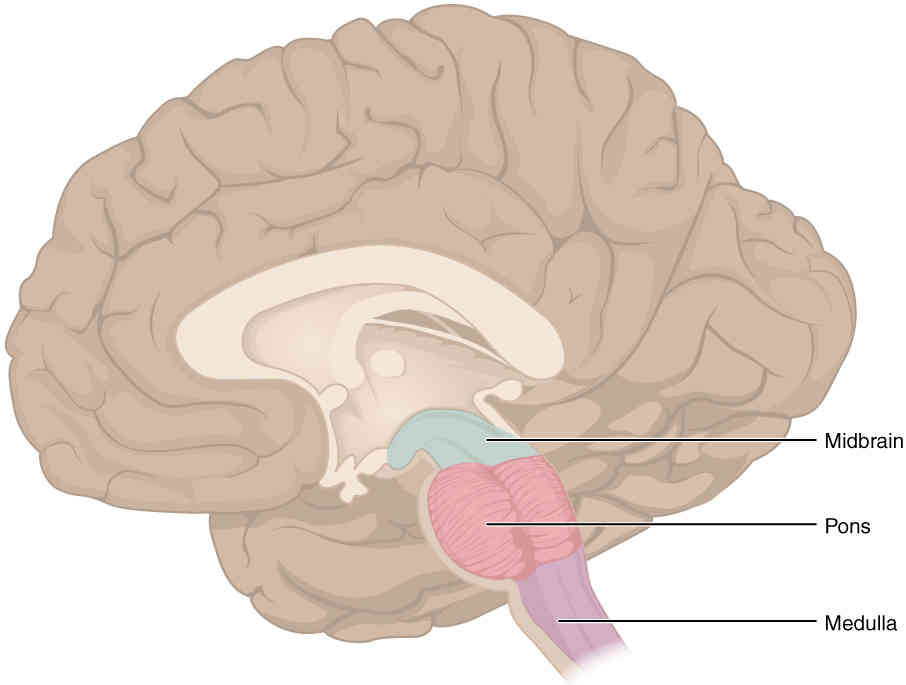

This page is under construction. For now, it is just a resource of the images found in the OpenStax Anatomy and Physiology Handbook. It wil slowly change into a revision tool. Each slide has a number. Use this to refer to the slide. When completed, it will have an unlabelled section, with labelled slides in parallel. On the unlabelled slides, write your answer and use the labelled slide to assess yourself. Keep track by also noting the number on each slide. Improvement at each attempt is important, more so than full marks on a first attempt.